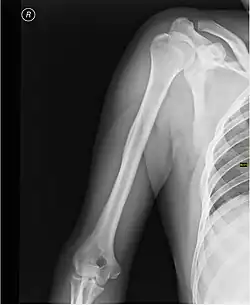

Скелет

Каркасом плеча служит плечевая кость.

При травмах плеча возможно повреждение нервов и сосудов, а также переломы плечевой кости, наиболее частой локализацией которых является шейка плечевой кости[1].